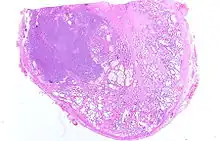

Histologie

Le diagnostic est obtenu par des biopsies prostatiques multiples, réalisées de manière échoguidée et par voie transrectale. Elle permet également de réaliser le score de Gleason, de grande valeur pronostique.

.jpg) Adénocarcinome prostatique

Adénocarcinome prostatique.jpg) Adénocarcinome prostatique

Adénocarcinome prostatique- Adénocarcinome ; tissus indifférenciés

Anatomopathologie

Le cancer entreprend la portion périphérique de la glande, au contraire de l'hypertrophie prostatique bénigne qui intéresse la zone centrale, périurétrale.